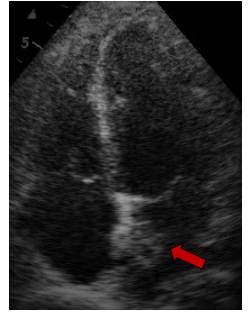

Γενικά, το διαθωρακικό υπερηχογράφημα (ακολουθείται σε μερικές περιπτώσεις από το διοισοφάγειο) είναι η πρώτη διαγνωστική εξέταση. Οι καρδιακοί όγκοι μπορεί να είναι ενδοκοιλοτικοί ή ενδομυοκαρδιακοί (ενδοτοιχωματικοί). Η ηχοκαρδιογραφία απεικονίζει τους ενδοκοιλοτικούς όγκους ως μία πυκνή υπερηχογενή μάζα ακίνητη με ευρεία βάση ή κινητή με μίσχο, που είναι προσαρτημένη στο ενδοκάρδιο. Αντίθετα, οι ενδοτοιχωματικοί όγκοι εμφανίζονται ως μία τοπική πάχυνση του μυοκαρδιακού τοιχώματος μίας κοιλίας. Οι καρδιακοί όγκοι μπορεί επίσης να προβάλλουν το περικάρδιο, με ή χωρίς συνύπαρξη περικαρδιακής συλλογής.

Τα σαρκώματα είναι τα πιο συνήθη από τα κακοήθη πρωτοπαθή νεοπλάσματα της καρδιάς. Η τυπική ηλικία εμφάνισης είναι μεταξύ 40 και 50 ετών. Στην ηχοκαρδιογραφία, εμφανίζονται ως μία μάζα με ευρεία βάση και ανομοιογενή ηχογένεια, συνήθως στο δεξιό κόλπο. Οι υπόηχες περιοχές εντός του όγκου αντιστοιχούν σε εστίες νέκρωσης του όγκου.

Εκτός από το δεξιό κόλπο που είναι η συχνότερη εντόπιση, μπορούν επίσης να εμφανιστούν σε οποιαδήποτε καρδιακή κοιλότητα και συχνά προσβάλλουν το περικάρδιο, με αποτέλεσμα την περικαρδιακή συλλογή και το θωρακικό άλγος από ερεθισμό του περικαρδίου. Όταν βρίσκονται σε μία δεξιά καρδιακή κοιλότητα, μπορούν να προκαλέσουν διαταραχή στη λειτουργία της τριγλώχινας βαλβίδας, να προκαλέσουν κλινικές εκδηλώσεις δεξιάς καρδιακής ανεπάρκειας και / ή να εμφανίσουν μεταστάσεις στους πνεύμονες. Η διαφορική διάγνωση είναι με το μύξωμα. Σε αντίθεση με τα μυξώματα, τα σαρκώματα δεν έχουν μίσχο. Τα σαρκώματα τείνουν να έχουν ταχεία ανάπτυξη, παρακωλύοντας τη ροή του αίματος. Η αντιμετώπιση με χειρουργική εκτομή του όγκου είναι εφικτή σε μερικές περιπτώσεις. Οι κακοήθεις πρωτοπαθείς καρδιακοί όγκοι είναι εξαιρετικά σπάνιοι. Σε σχεδόν όλες τις περιπτώσεις πρόκειται για σαρκώματα, με το αγγειοσάρκωμα να είναι το πιο σύνηθες μεταξύ αυτών. Τα σαρκώματα μπορούν να εμφανιστούν σε οποιαδήποτε καρδιακή κοιλότητα, αλλά βρίσκονται συχνότερα στον δεξιό ή τον αριστερό κόλπο. Οι κακοήθεις καρδιακοί όγκοι έχουν κακή πρόγνωση.